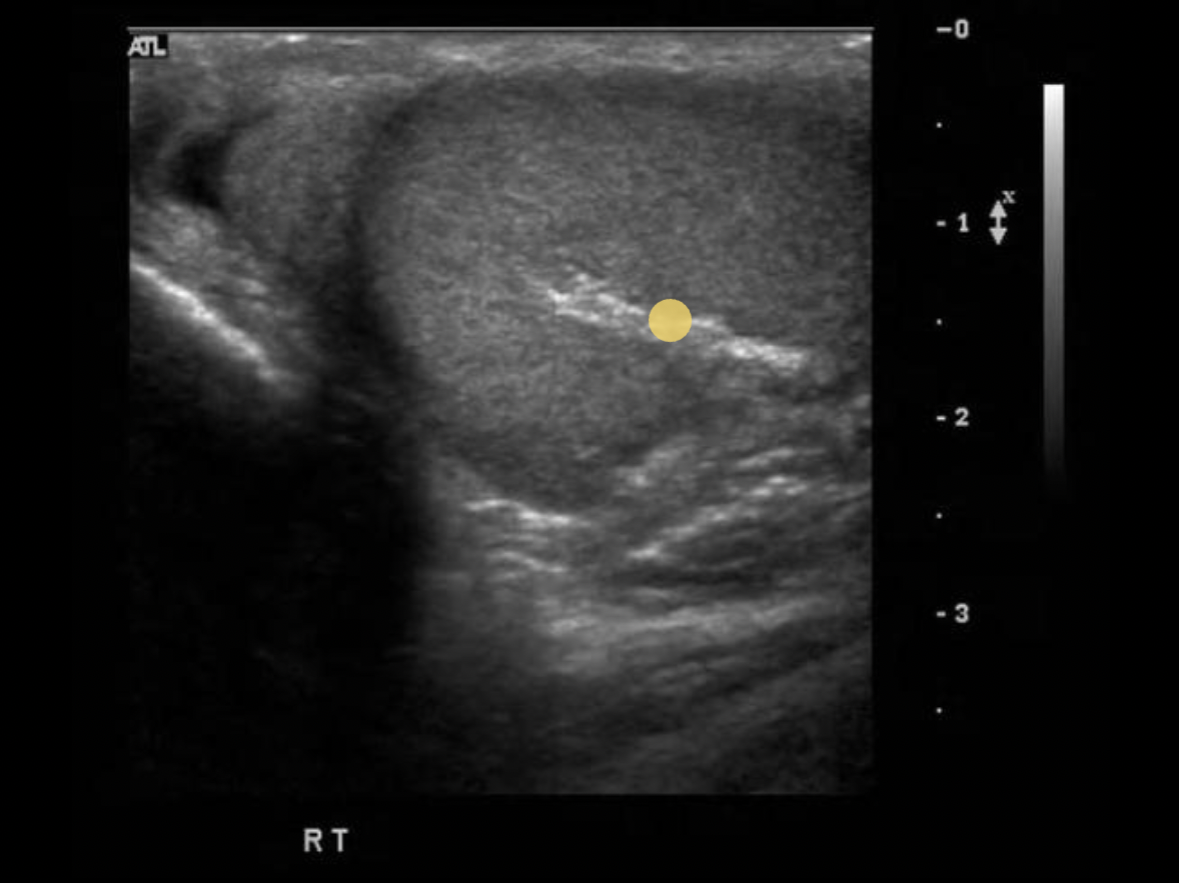

Find the mediastinum testis

The mediastinum testis is an infolding of the tunica albuginea that enters the posterior testicle. Blood vessels and tubules enter and exit the testicle through the mediastinum. testis. and it can be considered the hilum of the testicle.